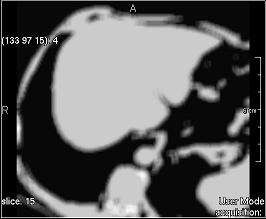

Average (simple)

../../../Modules/ML/MLFilter2/mhelp/Images/TextureFilterImages/average.jpg